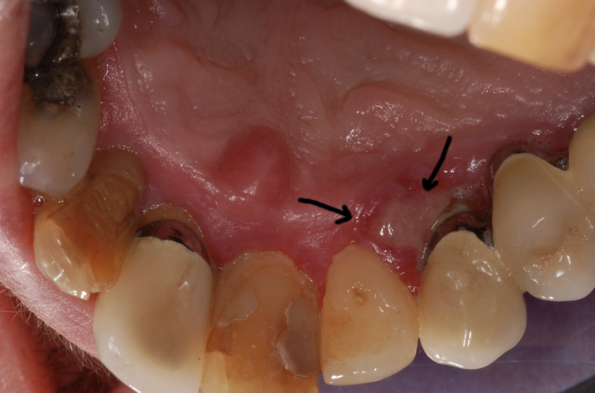

Infatti questi grossi ammassi rossastri, a volte mobili e sempre rilevati, abbracciano due elementi dentali creando notevoli inestetismi.

(Nella foto: epulide su protesi fissa)

Nei quadri clinici riportati si può notare la difformità di forma, di colore, di grandezza e di posizionamento che l’epulide può mostrare.